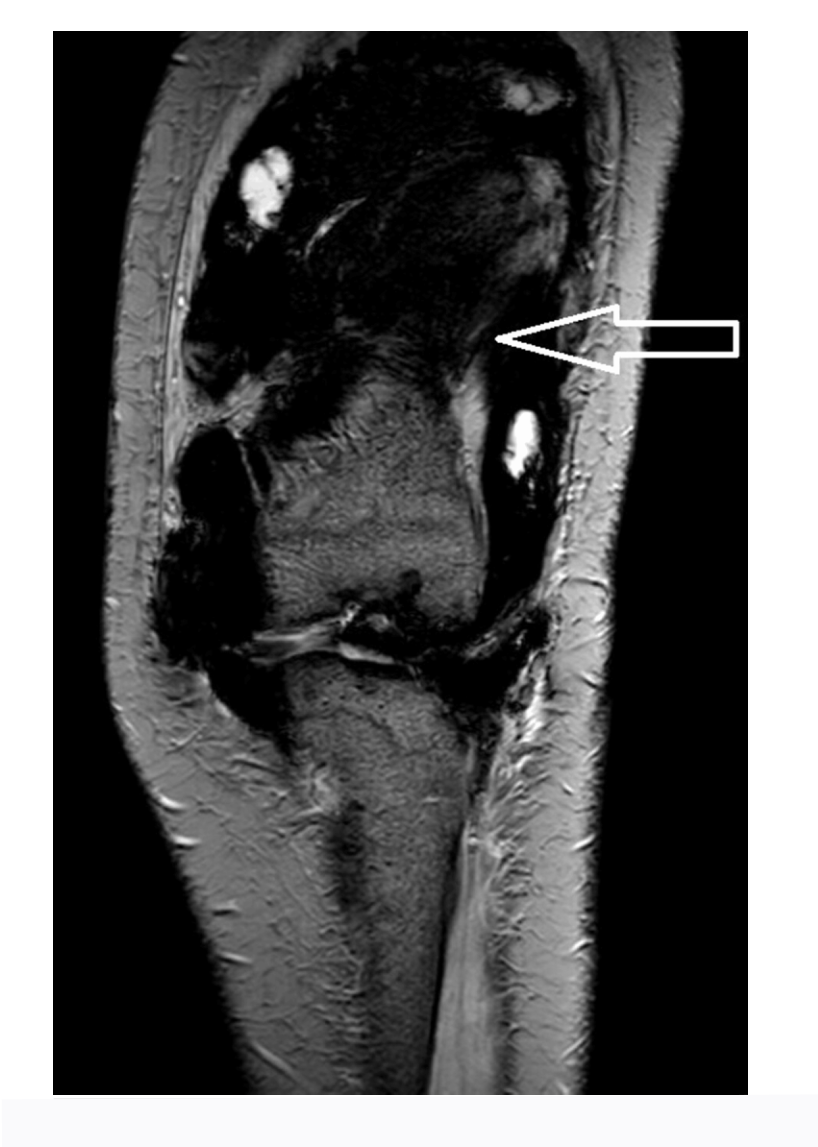

3.2 Resonancia magnética (RM) - Técnica de elección

- 🔹 Hallazgo clave: depósitos de hemosiderina que causan hipointensidad marcada en secuencias T2 y eco de gradiente (GRE) (por efecto de susceptibilidad magnética). Este hallazgo es altamente sugestivo de SVNP.

- 🔹 T1: Masas sinoviales de señal intermedia (similar al músculo).

- 🔹 T2: Combinación de áreas de alta señal (sinovial congestionada, líquido) y áreas de señal media-baja (depósitos de hemosiderina).

- 🔹 Tras contraste (gadolinio): Realce de la cápsula sinovial y de los septos. Las masas sinoviales pueden realzar de forma heterogénea.

- 🔹 La RM es lo suficientemente fiable para el diagnóstico, raramente necesitándose artroscopia diagnóstica.

Hallazgo radiológico característico